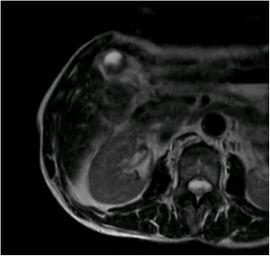

CT検査にて胆嚢底部に限局性に壁肥厚を認め、精査の結果、悪性病変疑いと診断。腹腔鏡下胆嚢摘出術を施行した。病理結果は胆嚢がんであった。

MRI画像